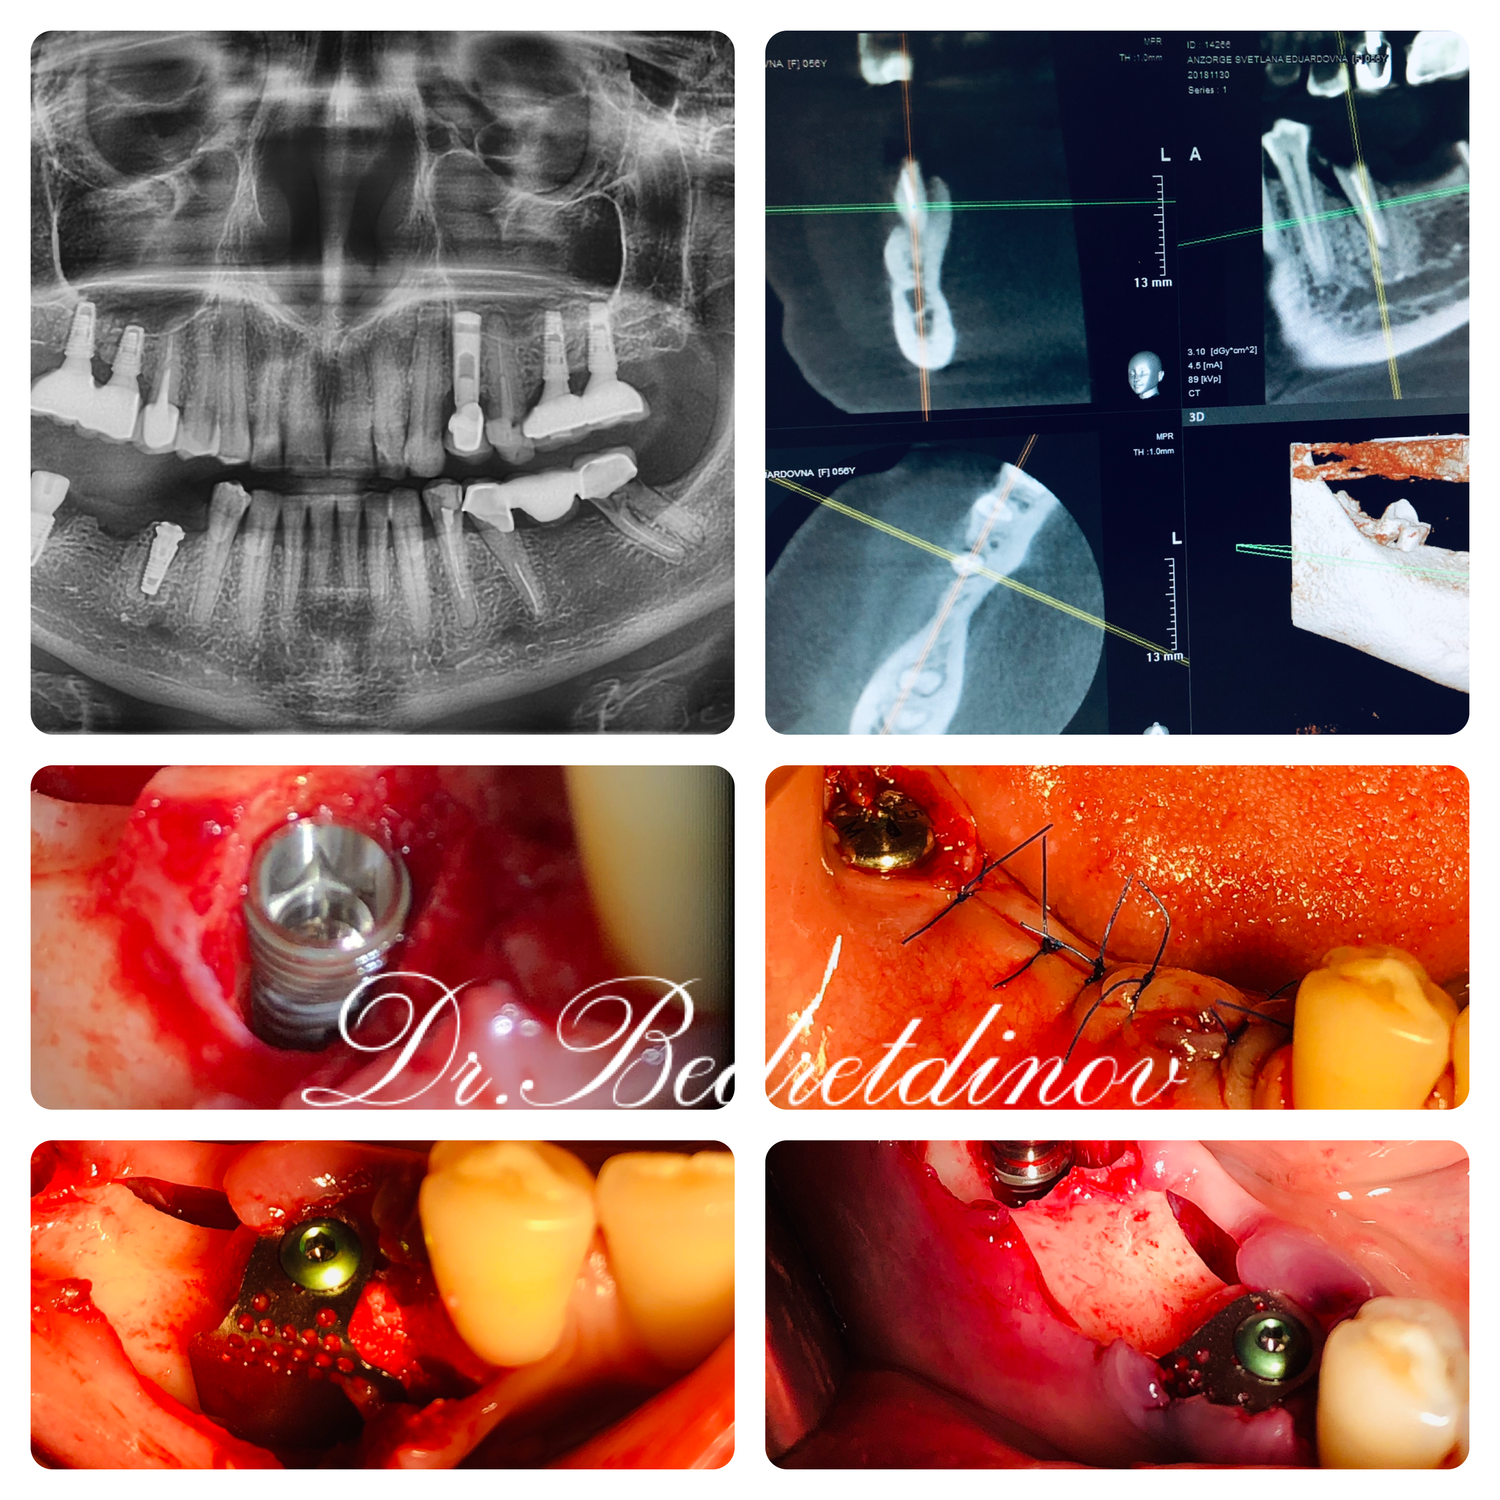

Read MoreУдаление зубов 4.5,4.7 с одномоментной дентальной имплантацией с фиксацией титановой сетки JEIL в области 45